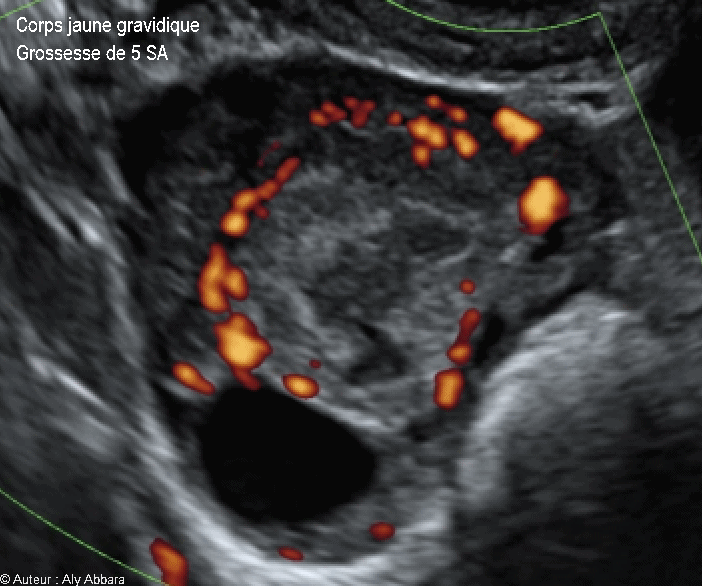

Corps jaune gravidique dans l'ovaire droit - Doppler Energie - جسم أصفر حملي في المبيض الأيمن

Corps jaune gravidique dans l'ovaire droit - Doppler Energie - جسم أصفر حملي في المبيض الأيمن -  5 SA

• Vidéo et image animée échographiques montrant un corps jaune gravidique, dans l'ovaire, chez une femme enceinte de 5 SA :